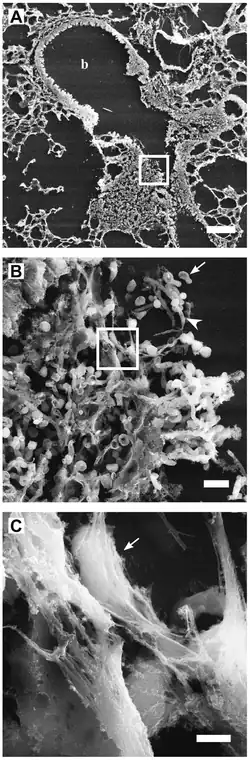

High-resolution scanning electron microscopy has shown that NETs consist of stretches of DNA and globular protein domains with diameters of 15–17 nm and 25 nm, respectively. These aggregate into larger threads with a diameter of 50 nm.[2] However, under flow conditions, NETs can form much larger structures, reaching hundreds of nanometers in length and width.[4]

More recently, it has also been shown that not only bacteria but also pathogenic fungi such as Candida albicans induce neutrophils to form NETs that capture and kill C. albicans hyphal as well as yeast-form cells.[9] NETs have also been documented in association with Plasmodium falciparum infections in children.[10]